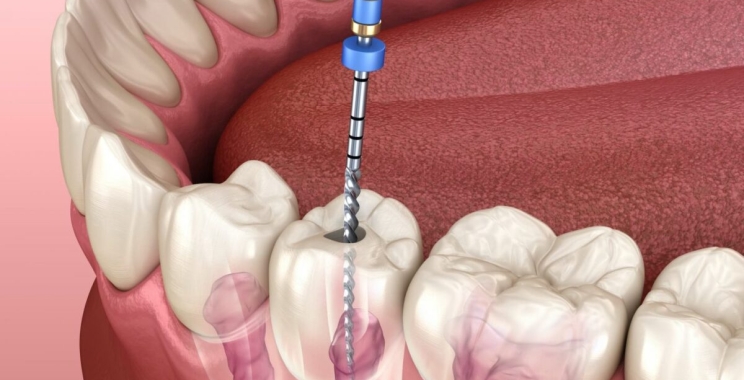

التهاب في اللب الداخلي:

ينتج عن التهاب في اللب الداخلي المحتوي على الأوعية الدموية والأعصاب ألم شديد في الأسنان، حيث أنه السبب الرئيسي، وبالتالي الصداع.